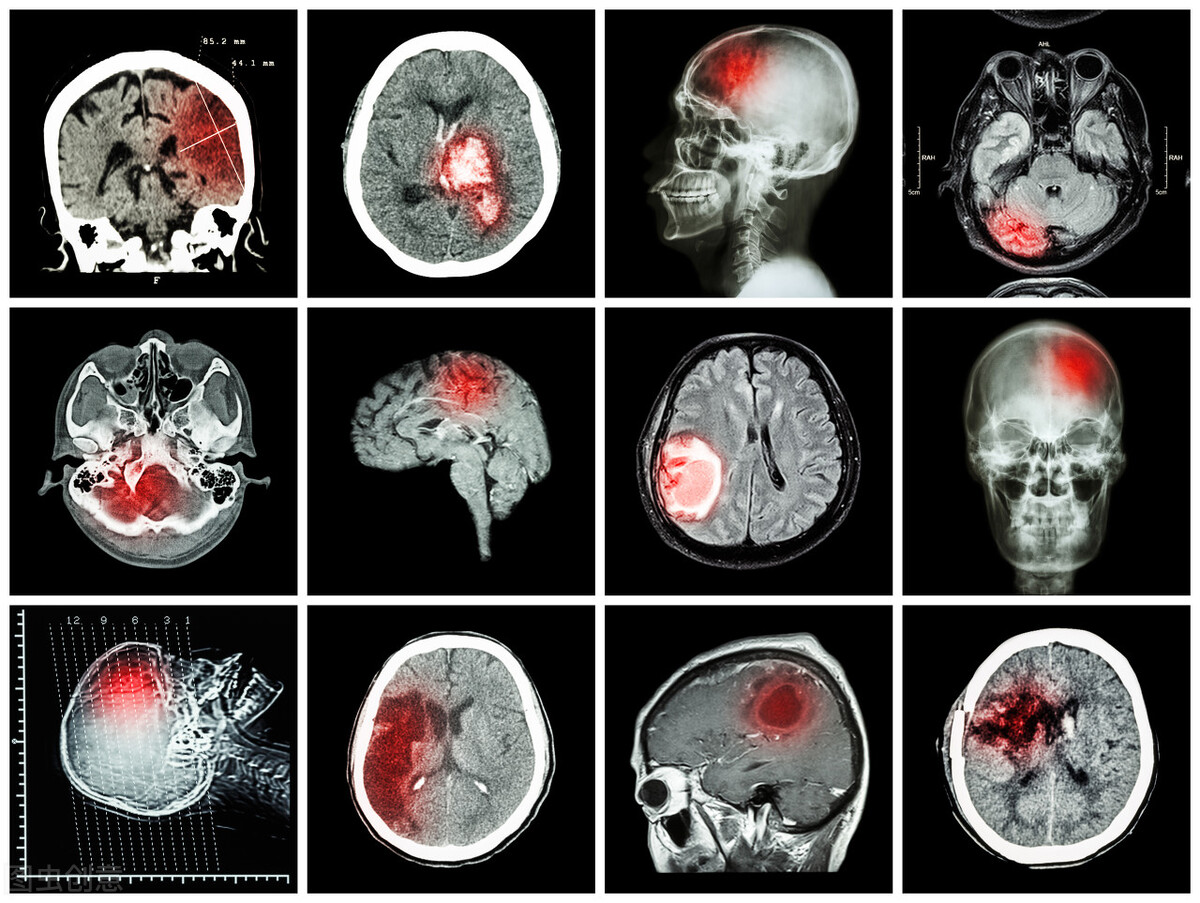

颈动脉是给我们大脑供血的动脉血管,两侧脖子各有一条。

这个地方如果出现狭窄堵塞,脑部供血就可能不足,从而引起头晕、乏力等症状,还可能诱发脑梗出现。

那么是这样的,因为脖子上血管通大脑的,这地方如果有狭窄,狭窄很重的情况下,那肯定会脑供血会有问题。

那么最常见的就像您说的症状,就是头晕。那么更严重一点,甚至出现短暂的意识丧失,我们叫短暂性脑缺血发作。这都有可能。

肯定会。因为本身有斑块之后,斑块情况如果不稳定,它就有破的可能性,那么局部就有血栓。一旦有血栓形成,那么到脑子这个就梗了。